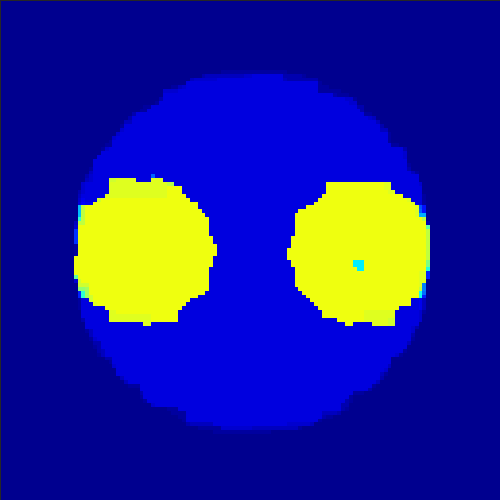

In order to test the behaviour of the proposed method in a more realistic, random-based test case, we performed a Monte Carlo simulation for dynamic SPECT imaging. First, we created a simple 129×129129129129\times 129 image phantom consisting of an outer and two inner circles which represents the structure of the region of interest (see figure 8(a)). Within those regions we assumed concentration curves over a time period of 90 time steps as displayed in figure 8(b). Based on the tracer intensity in an image frame at each time step, we created a variable number of random decay events (where the number is proportional to the average concentration in one pixel in the whole image frame per time step) with a probability proportional to the concentration in every subregion. They are detected by a virtual double head gamma camera rotating around the patient by 46 degrees per time step, which consists of 374 detector bins. Every simulated decay event is projected onto the scanner and counted by the corresponding detector bin.

Refer to caption

Figure 8: Monte Carlo simulation. Region 1 corresponds to the outer circle, region 2 to the two inner circles.

In two different tests we fixed the number of events counted by the detector equal to λ=20000𝜆20000\lambda=20000 (resp. λ=200000𝜆200000\lambda=200000) times the average concentration in one pixel. The resulting sinogram images of the accumulated counts in each bin are shown in figure 9.

Based on the sinogram data we applied the proposed algorithm in order to reconstruct the original image sequence. The results for both test cases are shown in figure 10.

As one can see, the method is able to reconstruct the regions properly, even in case of a low count number. Within a number of iterations (average of 100 outer and 10000 inner iterations), the algorithm presents a reasonable reconstruction of the region of interest and the corresponding regional tracer concentration curves. Here, the parameters were not optimized as in the case of the synthesized data sets in the previous section, but kept fixed as α=0.5𝛼0.5\alpha=0.5, β=0.1𝛽0.1\beta=0.1 and δ=1.5𝛿1.5\delta=1.5. With futher optimized parameter values one could possibly provide even better results.